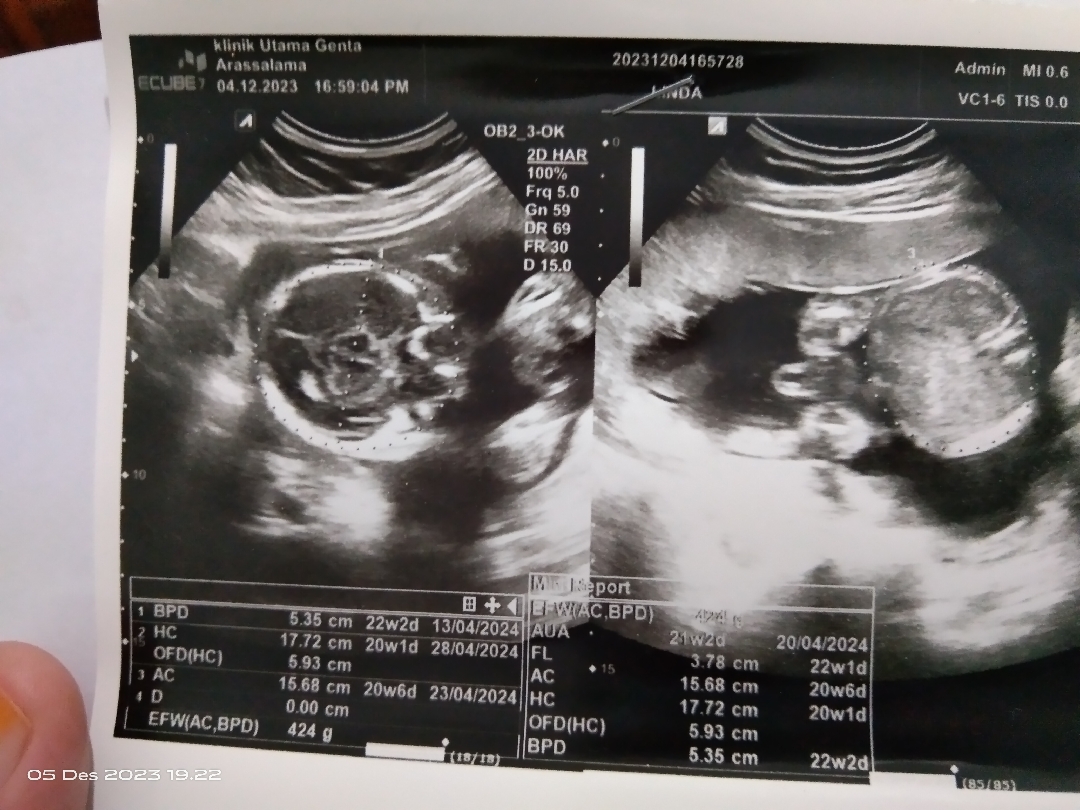

Hasil usg

Bunda, mau tanya pendapatnya ya :) ini hasil usg saya di week ke 20 bulan desember lalu. Disini dokter bilang katanya JK nya kemungkinan besar laki-laki karena jelas banget monasnya kayak digambar sebelah kanan, tapi sebulan kemudian saya usg kembali tapi kebetulan beda dokter karena dokter yang seharusnya berhalangan hadir nah disana jk nya tiba2 dibilang perempuan. Menurut bunda-bunda bagaimana? Apakah ini meyakinkan JK nya laki-laki? Terimakasih ♥️

Hasil yg kedua dikasih liat juga ga Bun? Itu jelas2 laki2 kok